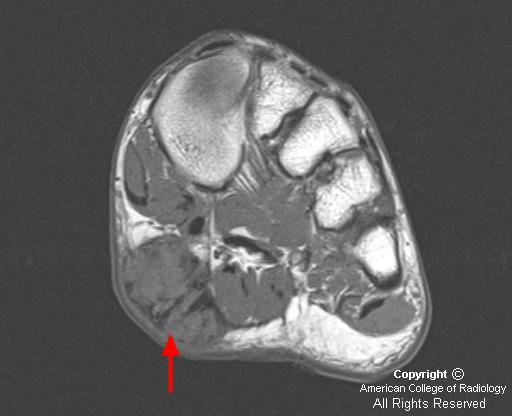

Плантарный фиброматоз (синдром Леддерхозе, описан им в 1897 г) в отличие от пальмарного фиброматоза редко сопровождается сгибательиой контрактурой. Поражает обычно медиальный отдел подошвы стопы (плантарный апоневроз) и имеет вид узелков, с течением времени достигающих 4—5 см в поперечнике. Узлы обычно плотные, множественные, связаны с фасциальными образованиями. Микроскопически новообразованная ткань богата фибробластоподобиыми клетками.

Подошвенный фиброматоз

Плантарный фиброматоз